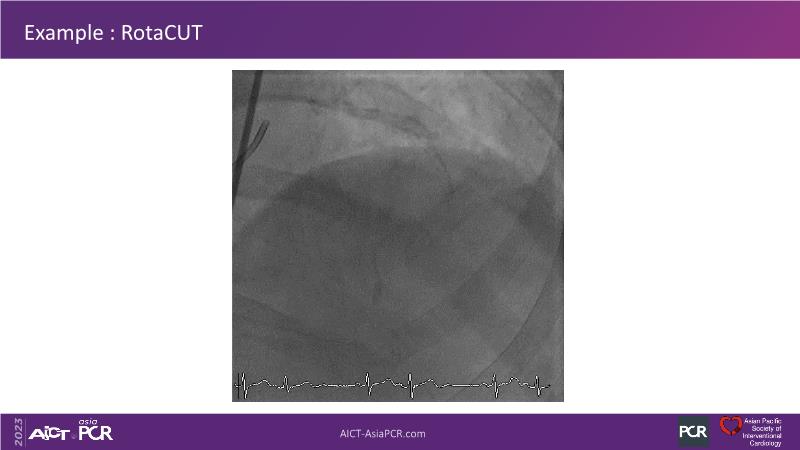

• To see advantages of RotaCUT as part of lesion preparation in left main bifurcation